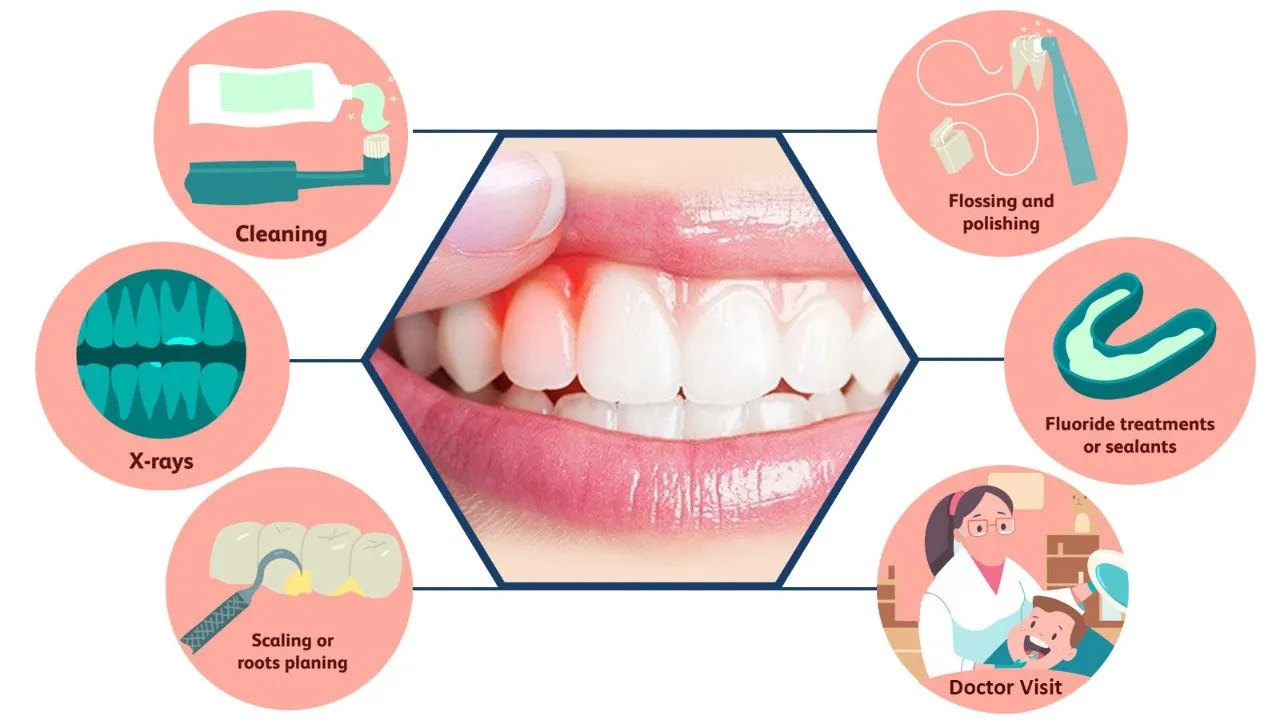

Our Gum Disease Treatment Options

The treatment facility at EZ Dental Care LLC provides several modern solutions to manage gum diseases effectively.

Deep Cleaning for Gum Disease

The performance of Scaling and Root planning functions to remove below-gumline plaque and tartar then makes root surfaces smooth for reducing regrowth.

Laser Gum Treatment

The non-surgical periodontal treatment uses light energy to treat infected tissue so patients experience quick recovery with little discomfort.

Antibiotic Therapy

Medicated ointment or prescribed medication through the mouth helps destroy bacterial growth and manage dental infections.

Surgical Solutions

We perform flap surgery combined with bone grafting procedures to treat serious gum disease which helps maintain gum condition.

Maintenance Therapy

Periodontal maintenance treatments should be done continuously so recurrence is prevented while maintaining the lasting health of the gum tissue.